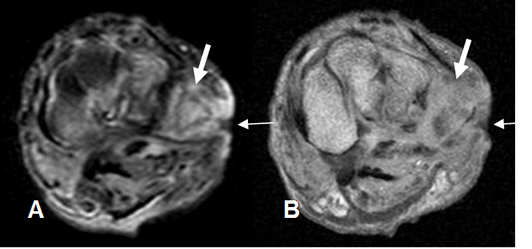

Fig 128 B. Fístula.

A: RM axial en T2 y B: RM axial en T1 con contraste. Defecto cutáneo en la parte externa del pie, que corresponde a úlcera. (Flechas delgadas). Los tejidos blandos adyacentes son hiperintensos en T2 y realzan con el contraste, por infección asociada. (Flechas gruesas).